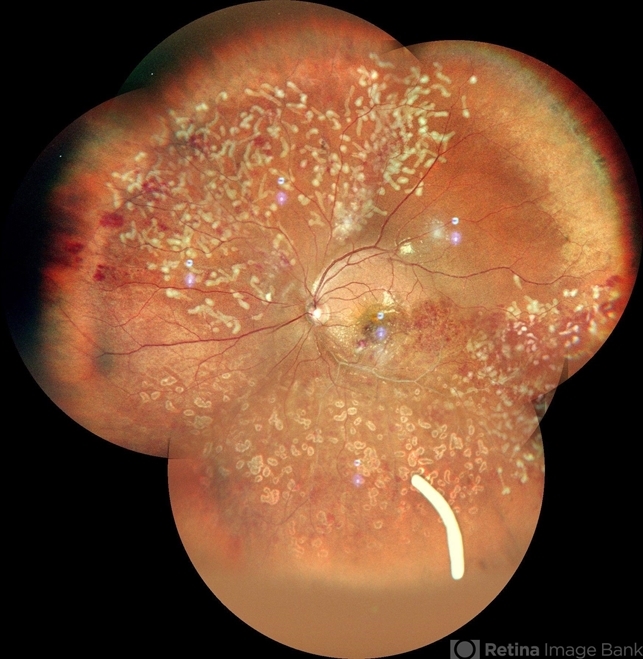

- laser photocoagulation, Ozurdex implant, idiopathic retinal vasculitis

- A color photo montage of an 32 year old male of LE showing laser marks in inferior and superior half with an floating ozurdex implant (inferiorly) in a case of idiopathic retinal vasculitis.